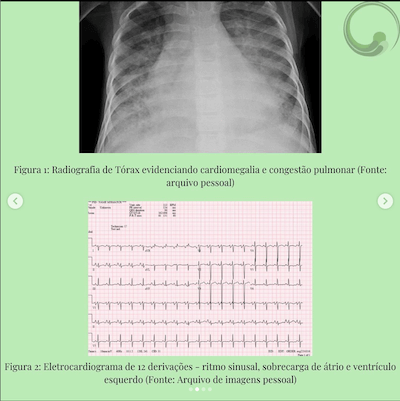

GI 5 anos, portadora de miocardiopatia dilatada sem causa definida, último ECO há 5 meses com FEVE 25%o, em uso de captopril zmg/kg/dia, carvedilol 0,3mg/kg/dia, furosemida 2 mg/kg/dia e espironolactona img/kg/dia. Paciente dá entrada no pronto socorro com quadro de febre há 2 dias, desconforto respiratório e tosse, mãe refere inapetência, prostração e redução da diurese hoje.

MV presentes e simétricos, estertores crepitantes em bases, taquidispneia moderada e tiragem subdiafragmática moderada. FR 40 ipm, Sat 94% em ar ambiente

RCR em 2 tempos, bulhas normofonéticas, presença de B3 intermitente, FC 120 bpm,

PA 70x40 mmHg